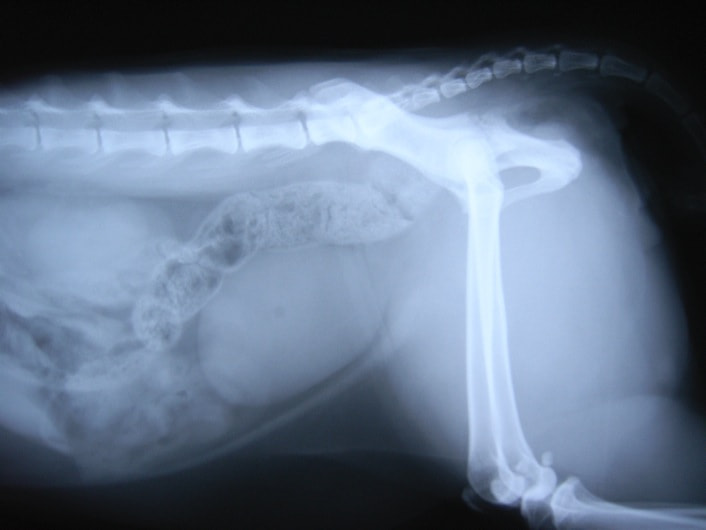

術前レントゲン